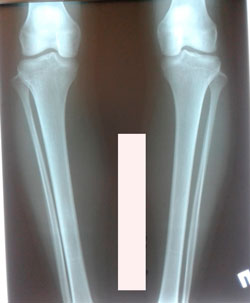

Исходник - 24 года.

Дата операции - 05.11.2020

Диагноз: Варусная деформация голеней + Ротация с обеих сторон.

Дата снятия аппаратов - 05.02.2021